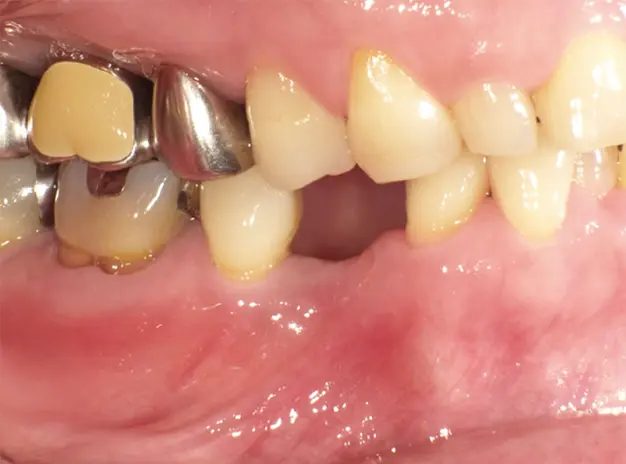

インプラント治療の症例をご紹介

【術前】 【インプラントの光機能化】 【術後】

インプラント治療の症例を紹介します。

下顎の小臼歯が欠損した50歳女性の方は、「自分の歯を極力削らない」「おいしく食事をしたい」「入れ歯の煩わしさから解放されたい」というご希望からインプラントを選択されました。見た目や機能の回復だけでなく、今後の健康維持のために原因への対処や定期的なメンテナンスに取り組まれています。

【治療部位】下顎

【治療期間】4ヶ月間

【治療回数】約10回

【リスク】インプラントが感染することがある

【治療費用】精密検査:16,000円(税込)

一次手術:227,000円(税込)

※手術管理費、仮歯代含む

上部構造:195,000円(税込)

※アバットメント代含む

合計:438,000円(税込)